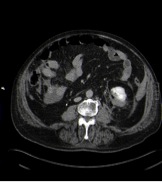

No se encuentra extravasado de contraste en la fase arterial por lo que se descarta lesión vascular. Existe una alteración de la anatomía normal del polo inferior del riñón izquierdo con solución de continuidad del parénquima (laceración) y una imagen en la parte posterior del mismo compatible con hematoma.